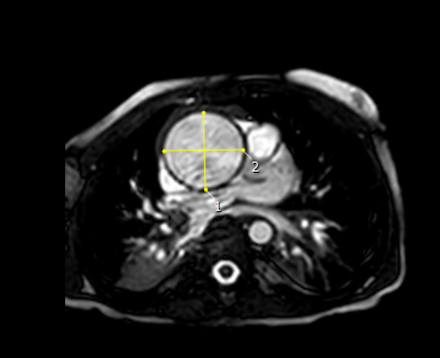

Results: Whole exome sequencing in a pediatric patient with an extreme, progressive TAA phenotype (4.0cm, Z-score +15) identified compound heterozygous nonsense mutations in EMILIN1, each inherited from one parent, as candidate causal variants. These variants (c.664C>T and c.1606C>T) were validated by Sanger sequencing. The EMILIN1 KO VSMCs demonstrated marked alterations in expression of genes encoding contractile apparatus and extracellular matrix proteins. Functional tests also revealed increased contractility (p=0.0374), decreased proliferation (p<0.0001), and decreased migration (p<0.0001) of EMILIN1 KO cells.